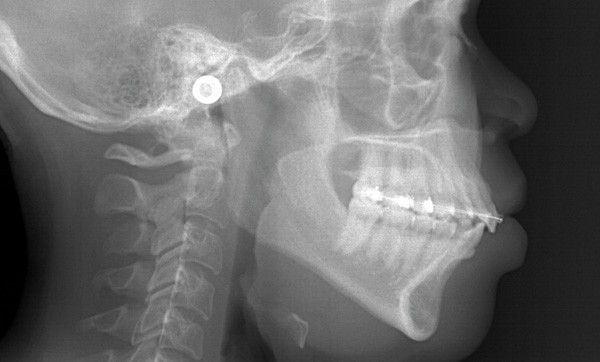

La patiente, outre une allergie au pollen, ne présente pas d’antécédents. L’examen parodontal initial révèle une enveloppe parodontale saine avec une gencive en « peau d’orange » et une pigmentation ethnique ; l’examen radio-clinique du secteur 14-24 met en évidence une hauteur de plus de 3 mm de gencive attachée, des poches vestibulaires et interproximales de 3 à 5 mm sans atteinte osseuse (fig. 3) ni migration de l’attache épithélio-conjonctive.